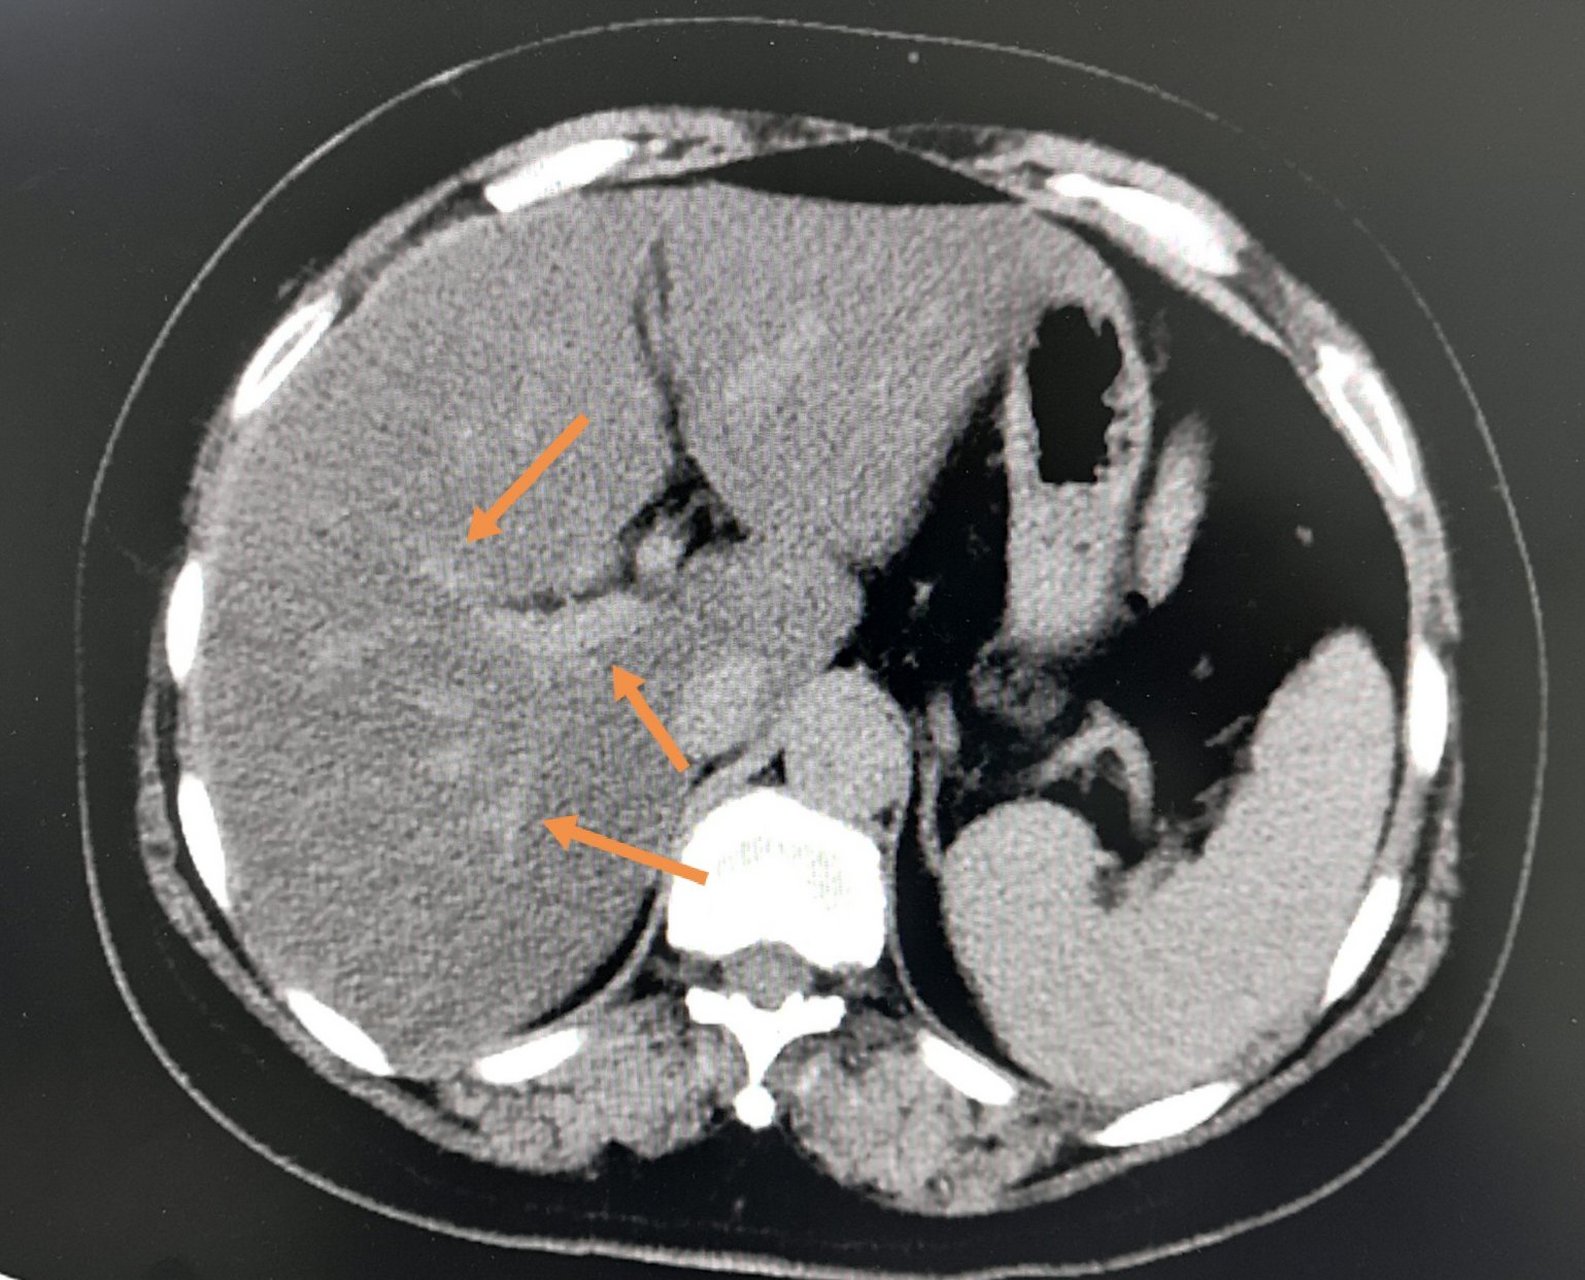

弥漫性脂肪肝伴正常肝岛一例ct增强病例

平扫显示肝的密度降低,弥漫性脂肪浸润表现全肝密度降低.

增强扫描,肝岛表现与脂肪浸润区同步均匀强化.